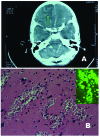

We report the first case of primary amebic meningoencephalitis in Italy, in a 9-year-old boy. Clinical course was fulminant, and diagnosis was made by identifying amebas in stained brain sections and by indirect immunofluorescence analysis. Naegleria fowleri was characterized as genotype I on the basis of polymerase chain reaction test results.